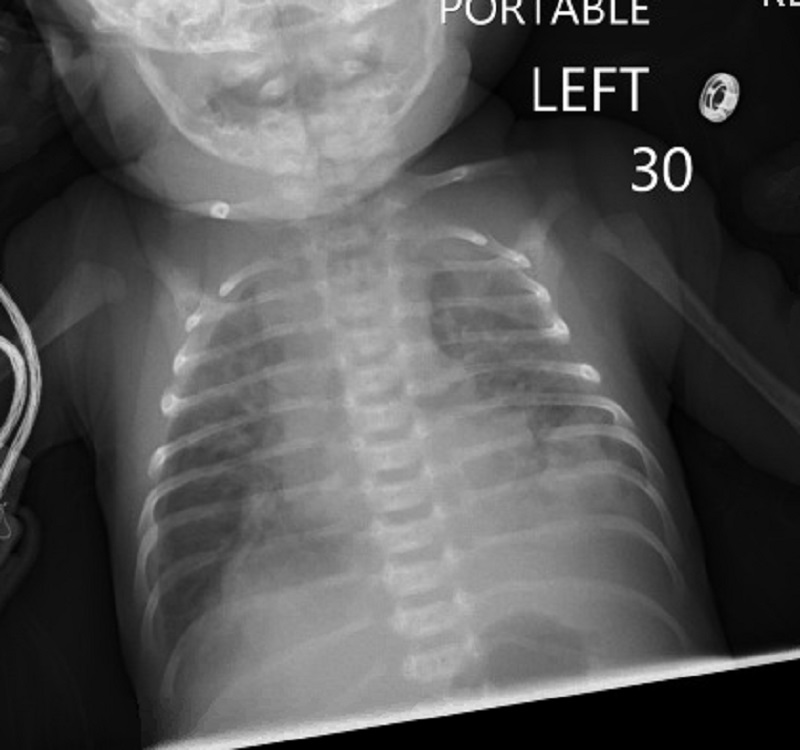

The patient was a 3-week-old Caucasian male born at term via C-section with a birth weight of 6lbs 4oz. Apart from fetal distress, there were no complications during the pregnancy or labor. The patient presented to the emergency department due to poor feeding, breathing difficulty, cough, and tachypnea over the course of 1 day. Evaluation showed the patient was hypoxic with 67% oxygen saturation on room air, and hypothermic with a temperature of 95.3F. Supplemental oxygen was given that improved the saturation. Chest x-ray showed bilateral pneumonia (Fig. 1). The baby was then transferred to the NICU.

Figure 1

Chest x-ray.